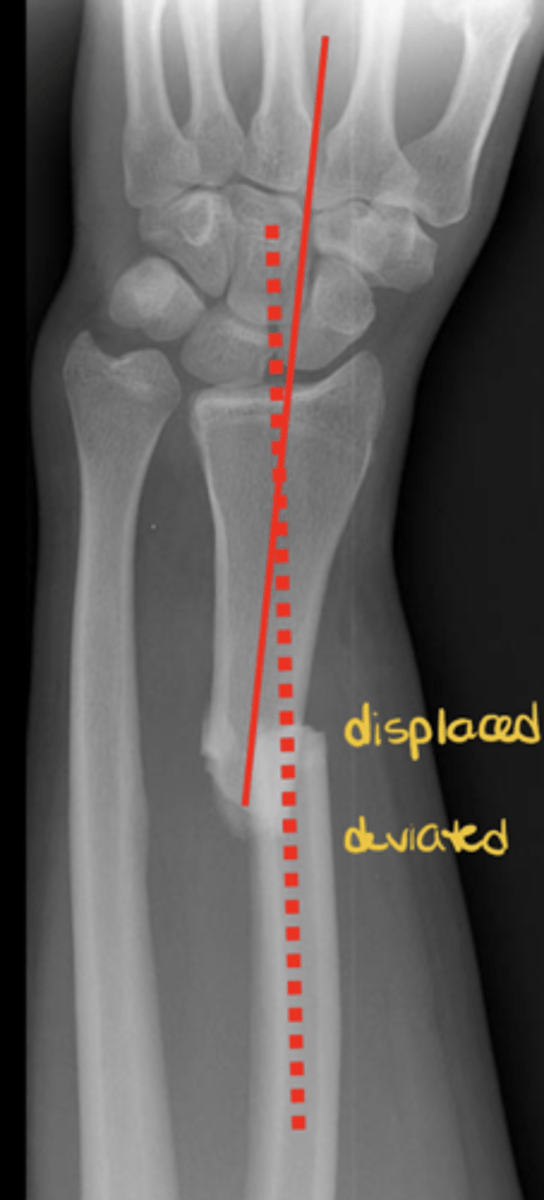

What does good position, good alignment look like vs. displaced with deviated alignment?

See image.

Name displacement based on the ________ fracture end in anatomical position

DISTAL!! -- i.e., "displaced medial, posterior, and overriding"

Name deviation based on the ________ bone angle in the ________ direction

DISTAL!! -- i.e., "deviated medial and anterior"